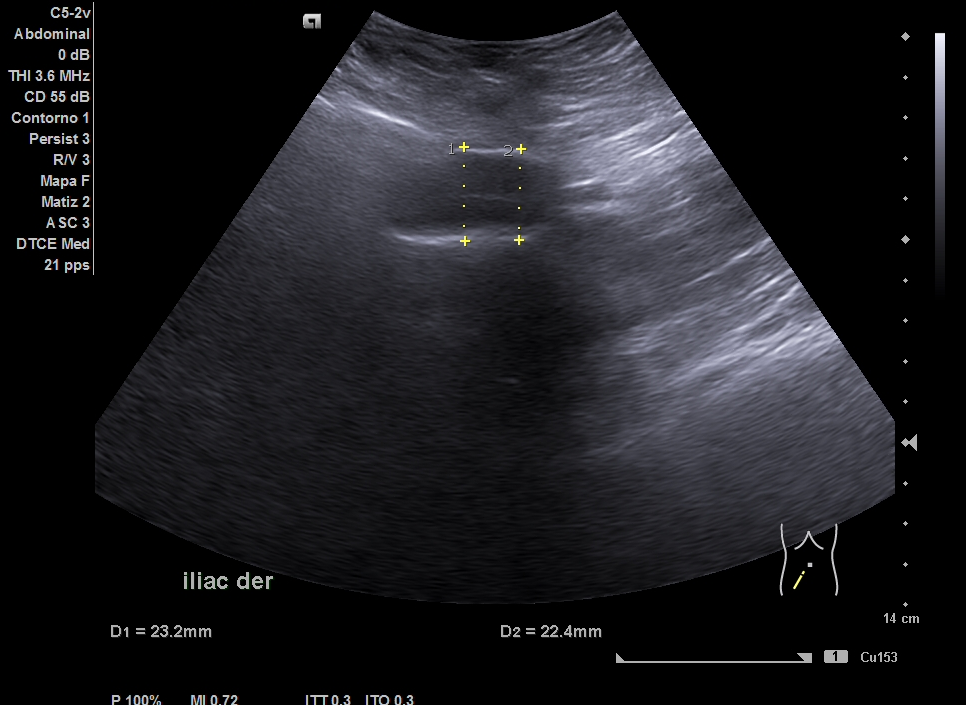

Parenquima hepatico sin alteraciones, vesícula biliar sin imagenes hiperecoénicas en interior. Pancreas visible en parte, sin alteraciones. Asimetría entre ambos riñones compatible variante de la normalidad RI. Llama la atención dilatación ilíaca derecha al comparar con contralateral y con aorta abdominal distal. Compatible con dilatación aneurismática ilíaca derecha.

El diagnóstico diferencial del Aneurisma Ilíaca con: Displasia fibromuscular u otra patología del tejido conectivo, lúes o tuberculosis entre otros. Toda dilatación que sobrepase el 50% del diámetro del vaso se considera aneurismática. Por la edad no se plantea el origen ateromatoso.

La ecografía en Atención Primaria se plantea en el contexto de responder a una pregunta clínica tras la anamnesis y la exploración física u otras pruebas complementarias que se precisen. A resaltar, la importancia de realizar ecografía completa siguiendo una sistemática y prestando atención tanto a variantes de la normalidad como a hallazgos patológicos. En el caso de la ecografía abdominal, es fundamental explorar los grandes vasos tanto en plano transversal como longitudinal, haciendo incapié en la división de las ilíacas.